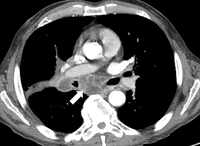

Linfadenopatia necrótica mediastinal

Dos acervos do Dr. Mario Gasparri e do Dr. Nicholas Choong

Veja esta imagem em contexto nas seguintes seções: